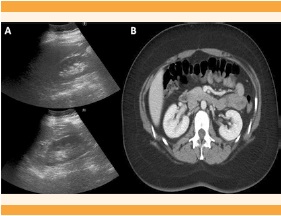

En la ecografía abdominopélvica se sospechó una malformación congénita uterina, pues se visualizó el útero izquierdo ligeramente tubular, de tamaño normal, con un pólipo endometrial en su interior, y adyacente a la imagen se observó una masa compatible con hemiútero derecho, de 52 x 49 mm, con contenido líquido hematológico retenido (hematometra) de 25 mm. El hemiútero no tenía conexión aparente con el cuello uterino ni con la porción contralateral del útero (Figura 1). El ovario izquierdo se visualizó de tamaño y características normales, con microfolículos y eje mayor de 3.2 cm, rodeando por fuera y por delante al ovario derecho, también de tamaño y aspecto normales; se observó una estructura quística alargada y en forma de codo, con contenido ecogénico de 65 x 15 mm, sugerente de hematosalpinx (Figura 2). La tomografía abdominopélvica confirmó la coexistencia del hemiútero derecho, de 55 x 54 mm, hipervascular, degenerado, con colección hemorrágica interna de 30 mm (Figura 3), e hidrosalpinx derecho. La ecografía y la tomografía no demostraron malformaciones renales. Figura 4

Figura 4 A) Ecografía pélvica que muestra los riñones sin alteraciones. B) Tomografía abdominal, corte transversal, con riñones sanos.